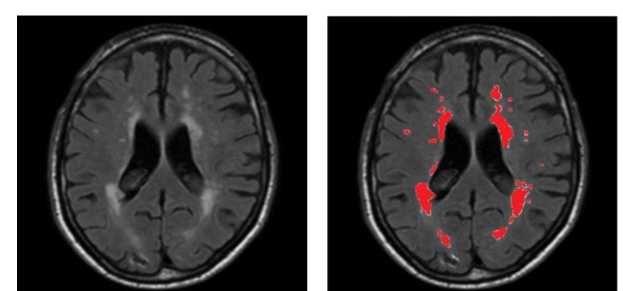

White matter lesions characterized by bilateral, mostly symmetrical hyperintensities, are commonly seen on FLAIR MRI of clinically healthy elderly people; furthermore, they have been repeatedly associated with various neurological and geriatric disorders such as mood problems and cognitive decline (Kim et al., 2008; Debette and Markus, 2010). Manual delineation of WMH area, as shown in Figure 1, is a reliable way to assess white matter abnormalities but this process is laborious and time-consuming for neuroradiologists and shows high intra-rater and inter-rater variability (Grimaud et al., 1996).

Refer to caption

Figure 1: A sample of MR slice from FLAIR modality (left), and its corresponding manual annotation of WMH by a neuroradiologist (right).